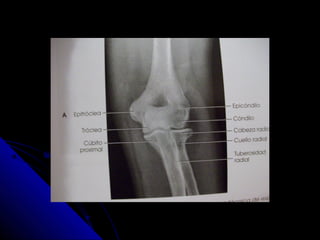

CODO. APCODO. AP

 Chassis 24 x 30 para las dosChassis 24 x 30 para las dos

proyecciones.proyecciones.

 Codo extendido y la mano en supinaciòn.Codo extendido y la mano en supinaciòn.

 R.C. perpendicular a la articulaciòn.R.C. perpendicular a la articulaciòn.

 Se ven: la cabeza, el cuello y laSe ven: la cabeza, el cuello y la

tuberosidad radiales ligeramentetuberosidad radiales ligeramente

superpuestos sobre el cùbito proximal.superpuestos sobre el cùbito proximal.

 Ausencia de rotaciòn de epicòndilo yAusencia de rotaciòn de epicòndilo y

epitroclea.epitroclea.

 En la proyección AP:En la proyección AP:

 el olècranon està oculto.el olècranon està oculto.

 El còndilo se articula con la cabeza radial ,El còndilo se articula con la cabeza radial ,

que es lateralque es lateral

 La tròclea se articula con el cùbito, que esLa tròclea se articula con el cùbito, que es

medial.medial.

 En la proyecciòn lateral:En la proyecciòn lateral:

 El còndilo y la troclea se superponenEl còndilo y la troclea se superponen

 En una rfìa lateral estricta se puede trazar unaEn una rfìa lateral estricta se puede trazar una

lìnea a lo largo de la cortical anterior dellìnea a lo largo de la cortical anterior del

hùmero. En la mayorìa de los pacientes, aprox,hùmero. En la mayorìa de los pacientes, aprox,

un tercio del còndilo es anterior a esta lìnea.un tercio del còndilo es anterior a esta lìnea.

 Si menos de un tercio del còndilo es anterior aSi menos de un tercio del còndilo es anterior a

esta lìnea , hay que sospechar una fracturaesta lìnea , hay que sospechar una fractura

supracondìlea con desplazamiento posterior delsupracondìlea con desplazamiento posterior del

fragmento distal.(esta norma no siempre esfragmento distal.(esta norma no siempre es

fiable en niños muy pequeños particularmentefiable en niños muy pequeños particularmente

cuando hay una osificaciòn parcial del còndilo.cuando hay una osificaciòn parcial del còndilo.

 Una lìnea trazada a lo largo del centro deUna lìnea trazada a lo largo del centro de

la diàfisis del radio proximal deberìa pasarla diàfisis del radio proximal deberìa pasar

a travès del còndilo.a travès del còndilo.

 Si esta lìnea no pasa a travès del còndilo,Si esta lìnea no pasa a travès del còndilo,

es probable la luxaciòn de la cabeza deles probable la luxaciòn de la cabeza del

radio.radio.

 Esta norma es siempre vàlida si se aplicaEsta norma es siempre vàlida si se aplica

a las rfìas que son estrictamente laterales.a las rfìas que son estrictamente laterales.